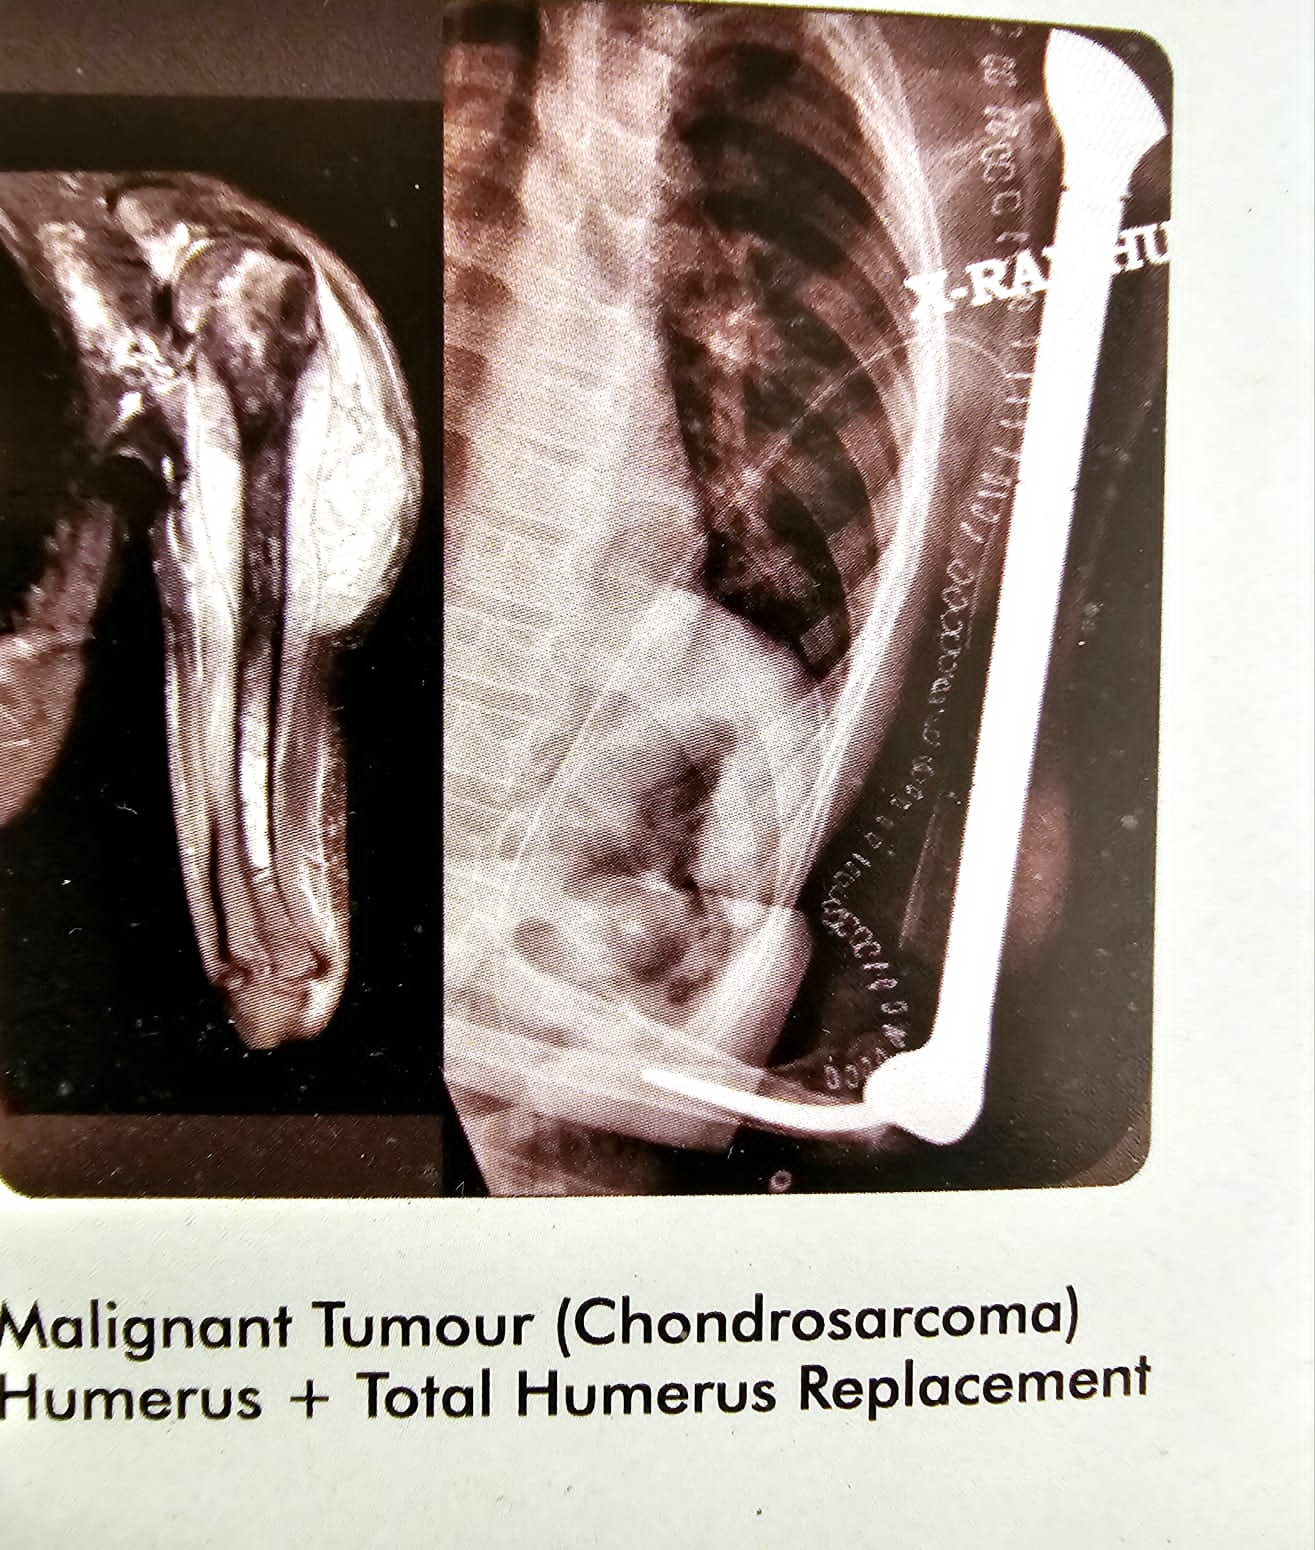

Malignant tumour (chondrosarcoma)

This is the case of malignant tumour chondrosarcoma of the humeral head and the proximal humeras in a seventeen year old boy from Nigeria. I replaced his entire humeras including the humeral head and also gave him an elbow. You can say a total humeral replacement with an elbow. Patient did very well, and continued to live for almost a year after the surgery, after that he succumbed to the malignant.

Malignant tumour (chondrosarcoma)

This is the case of malignant tumour chondrosarcoma of the humeral head and the proximal humeras in a seventeen year old boy from Nigeria. I replaced his entire humeras including the humeral head and also gave him an elbow. You can say a total humeral replacement with an elbow. Patient did very well, and continued to live for almost a year after the surgery, after that he succumbed to the malignant.